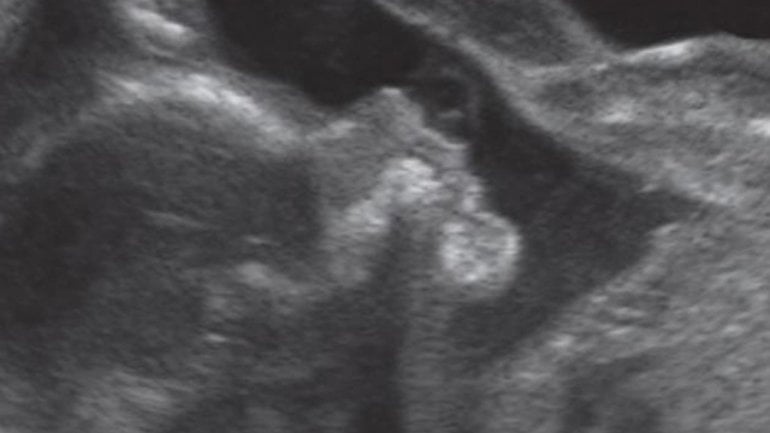

Ultraschall 32. SSW

Hier sieht man, dass dieses Baby ein Junge ist. Der kleine Penis ragt deutlich nach rechts ins Bild. Wenn das Baby günstig liegt, kann man schon um die 14. SSW das Geschlecht erkennen. Spätestens mit einem Ultraschallbild wie diesem ist dann aber klar, ob es ein Junge oder ein Mädchen wird.